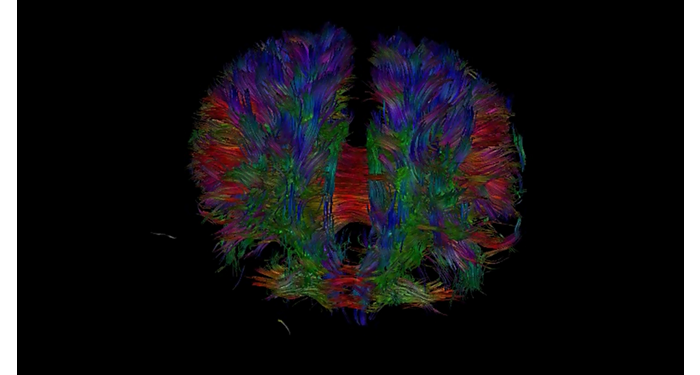

El 70% de los radiólogos consideran que las indicaciones neurológicas son un desafío, sobre todo debido a la falta de técnicas apropiadas de imagenología y visualización¹. Philips tiene como objetivo proporcionar la mejor claridad de diagnóstico posible y orientación terapéutica para todos los pacientes con trastornos neurológicos. Al aprovechar nuestra plataforma digital dStream, este año presentamos un conjunto de estrategias nuevas de imagenología y visualización. Esto puede ayudarlo a resolver preguntas sobre neurología complejas con mayor certeza, así como a desbloquear nuevos territorios neurológicos en aplicaciones neurofuncionales avanzadas. Este es un paso clave para aumentar el diagnóstico neurológico y, en última instancia, impactar más vidas con la RM. ¹ TMTG Market Survey 2016

Nuevas aplicaciones neurológicas